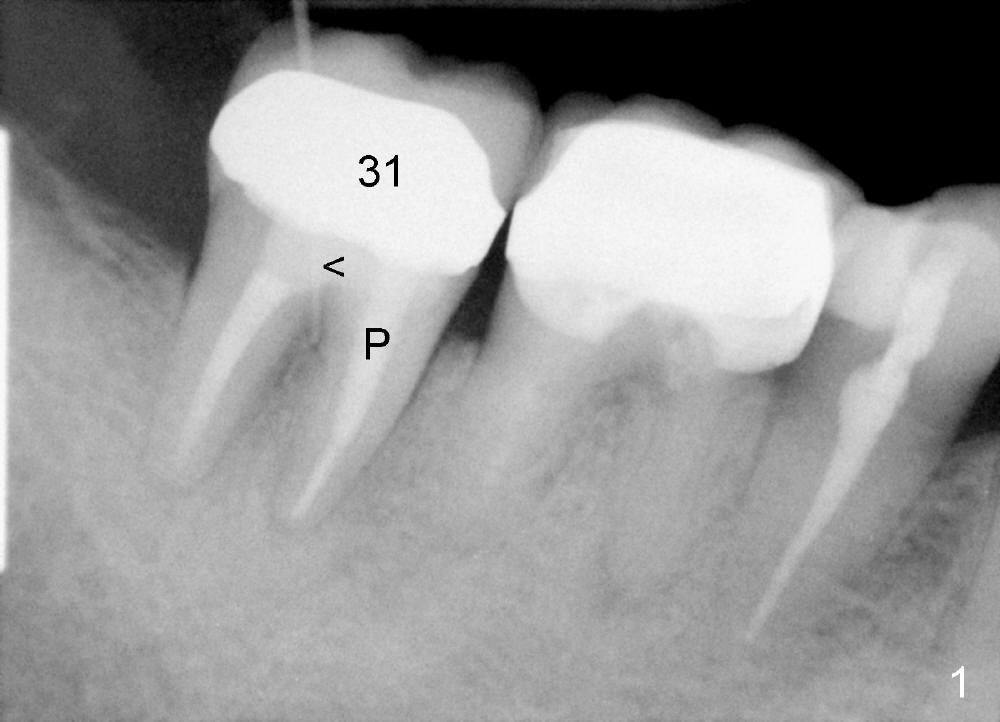

A 51-year-old man has experienced pain and swelling in the lower right 2nd molar for 7 months (Fig.1, P: post in the mesial root; <: gutta percha inserted into a buccal fistula). Fig.2 is taken immediately before extraction (<: purulent discharge from the mesiobuccal fistula) and immediate implant (Fig.3 implant design: 7x14 mm). A vertical root fracture is noted in the mesial root (Fig.4: lingual view). The septum is in fact absent, as compared to Fig.1. The mesiobuccal plate is low; the osteotomy starts lingual to the center of the socket. Fig.5 shows a 4.5x17 mm tap in place: approximately 3.5 mm in the new bone (~2.5 mm from the inferior alveolar canal). When a 7x17 mm tap (14 mm from the gingival margin) is placed in the socket, it looks relatively small. Fig.6 shows a 8x14 mm implant in place with a small gap distally. Mineralized cancellous allograft and Osteogen mixture is placed mainly buccally, followed by a thin strip of collagen dressing and sutures (Fig.7); an abutment (A) is placed to keep perio dressing in place. The perio dressing does not stay long. The buccal portion dislodges by itself 5 days postop. The lingual portion is removed in clinic. New dressing is going to be re-applied, because the buccal wound has not completely healed (Fig.8 <, albeit asymptomatic) with partial exposure of the bone graft (*). Why is the dressing lost so early? The abutment is not long enough; there is plenty of occlusal clearance (Fig.9 arrows). A longer abutment is used to increase mechanical retention for perio dressing (Fig.10). By the time the second perio dressing dislodges, the wound has healed (Fig.11, 13 days postop).